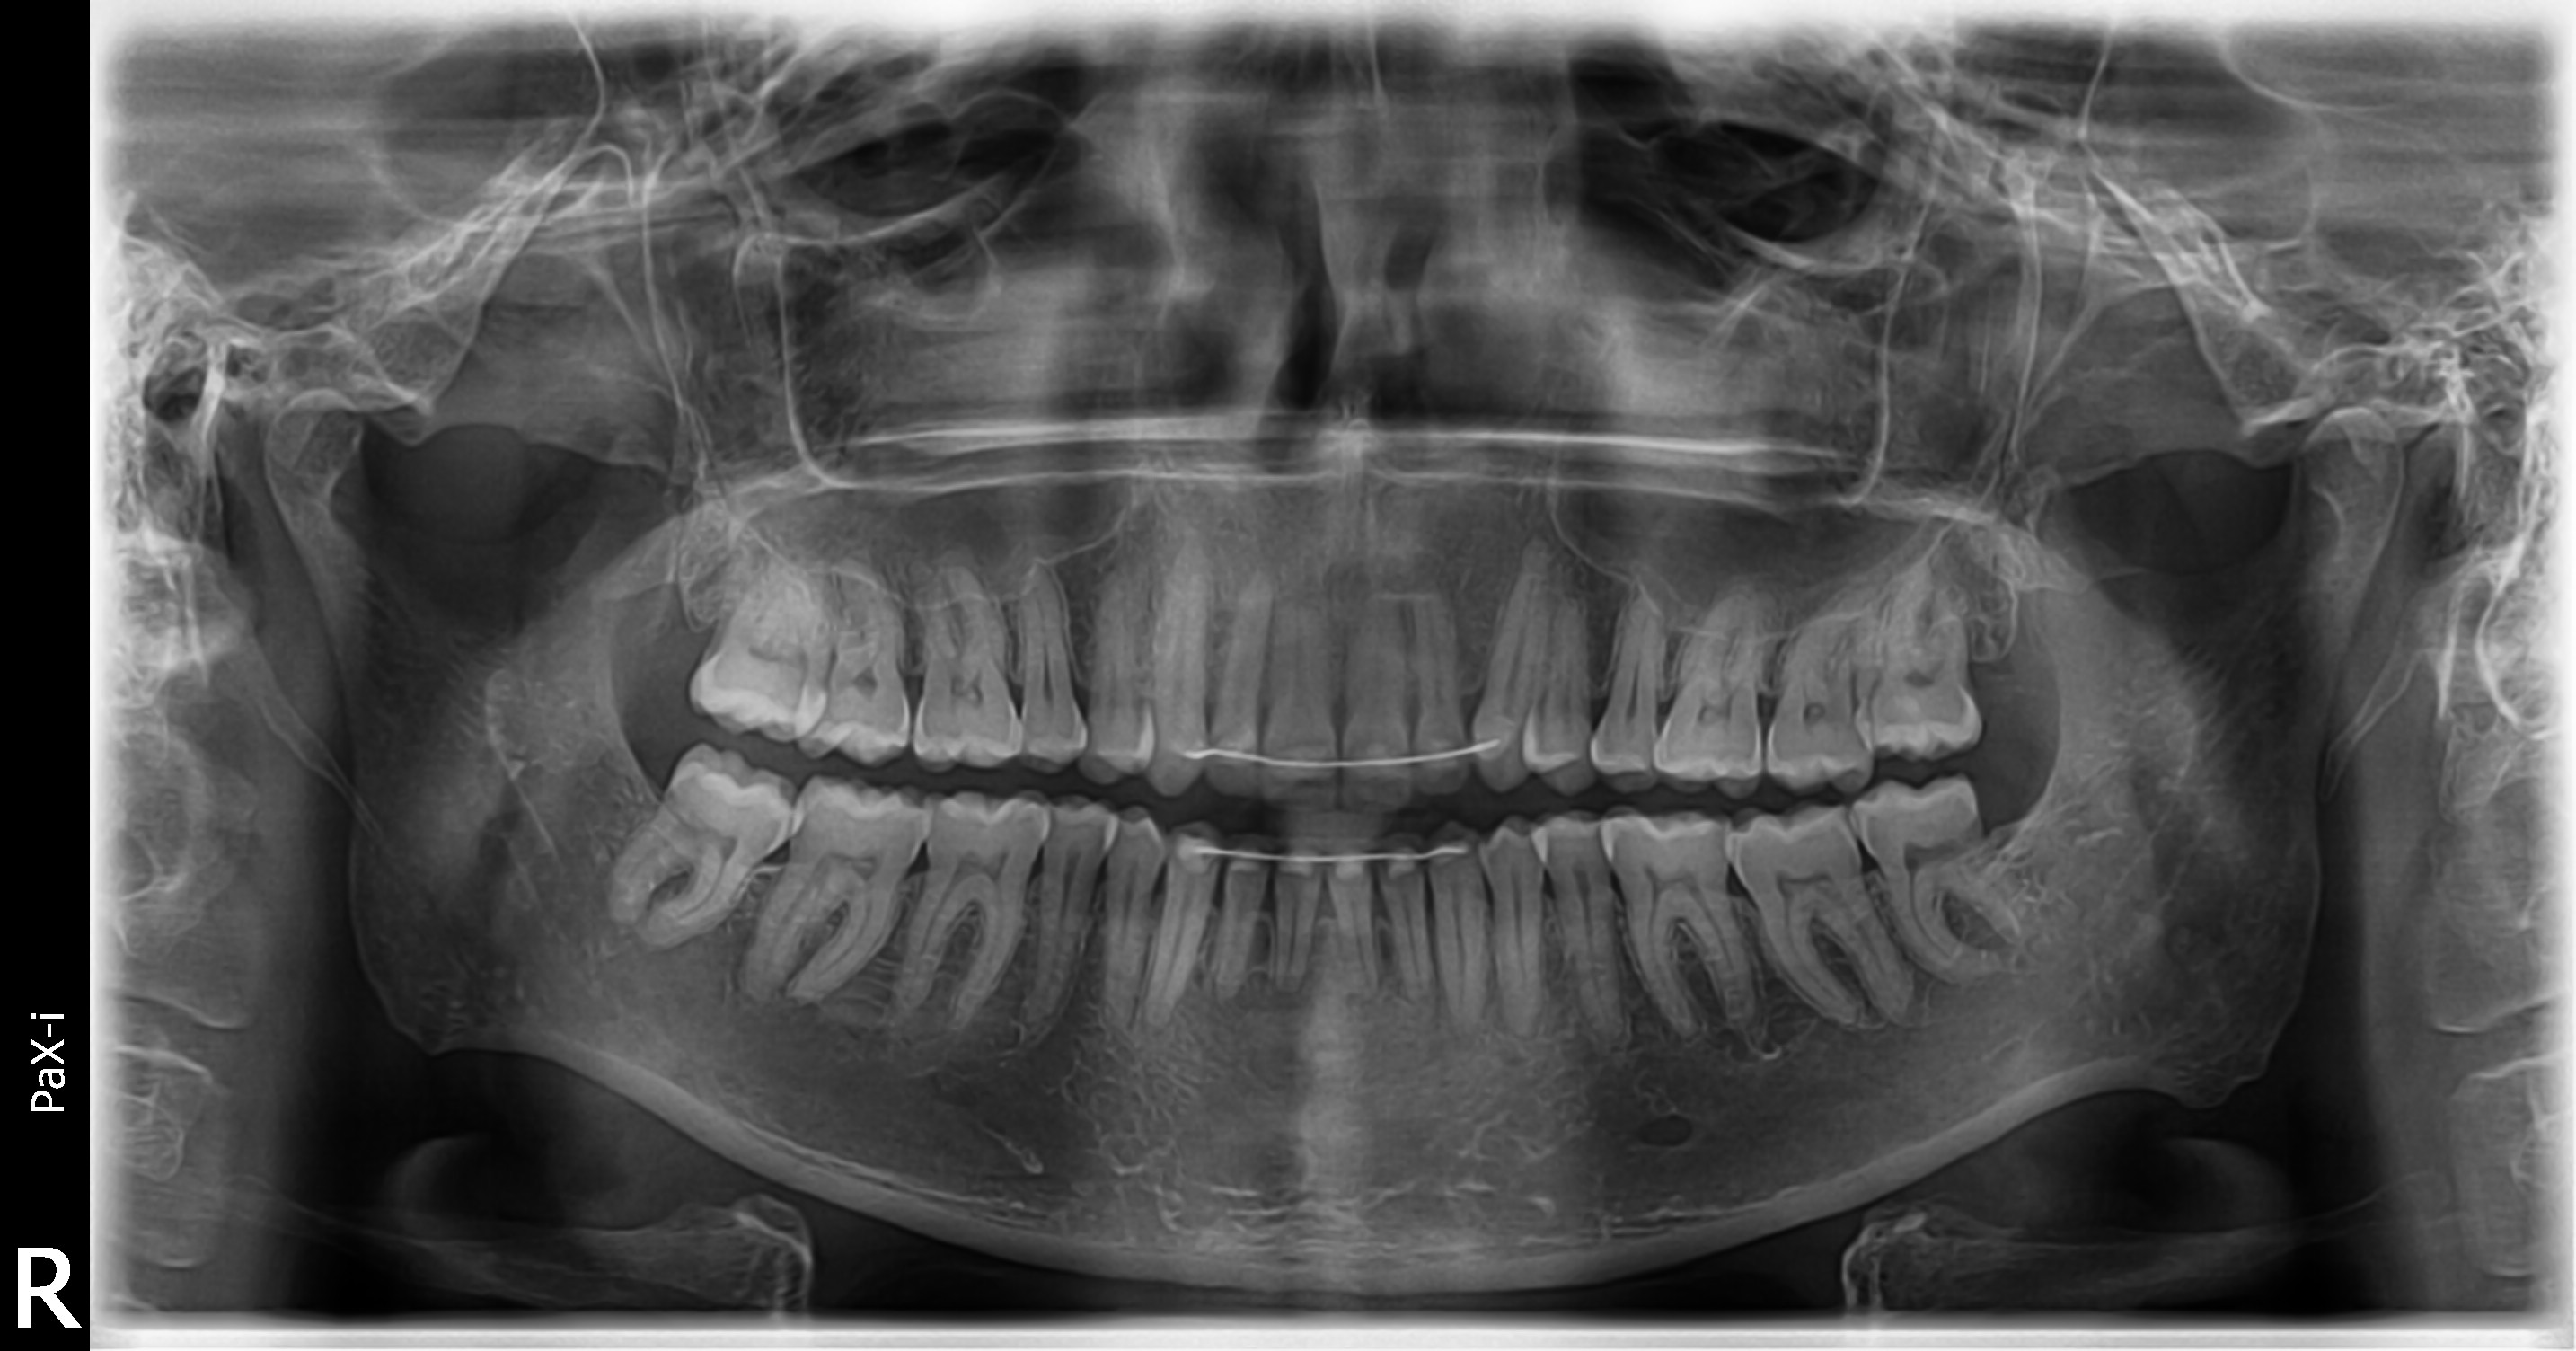

Vandaag is er een rontgenfoto gemaakt van mijn hele kaak. Ik vermoed dat dit een OPT wordt genoemd? De tandarts zag niets vreemds op de foto, geen ontstekingen, niets. Wel zag ze dat de wortels van mijn onderste voortanden korter zijn geworden t.o.v. eerdere foto van 6-7 jaar geleden. Dit komt waarschijnlijk door de beugel die ik heb gehad (en/of kaakklemmen) en het was niet iets om me zorgen over te maken, zei ze. Zelf schrok ik er wel van natuurlijk, want niemand vertelt je dat dit kan gebeuren voordat je een beugel neemt. Ik voel nog steeds af en toe mijn hoektand lichtjes "tikken", evenals een kies. Maar de tandarts heeft gekeken en zei dat er niets los zat. Dat zal dan wel zo zijn. Ik zal het maar moeten proberen los te laten (ha! "los"). Wellicht is er wat meer beweging in gekomen doordat ik de afgelopen paar weken het onderbitje ben gaan dragen ipv het bovenbitje. Bedankt voor uw reacties - heel fijn! :)

Daar heeft u gelijk in. Ik zal de foto uploaden. De verstandskies die afgelopen weekend ontstoken was (dwz het tandvlees eromheen) was linksonder (links voor mij, dus op de foto rechtsonder). Waar ik nu het getik voel is rechtsonder (rechts voor mijn, dus op de foto linksonder), de hoektand en volgens de kies ernaast.

Tandarts_Richa…

sorry zie de foto nu pas. Zo kan ik mij ook niet voorstellen dat er abnormale beweeglijkheid zou zijn maar kan dat niet zo v e foto aflezen. Zie in de boven kaak wel terug getrokken bot niveau. Zie ook wat er bedoeld wordt met de kortere wortels v d voortanden. Voor het terugtrekken v h bot zou ik overleggen met de mondhygienist/parodontoloog. Hoe zit het met de meting v h tandvlees. Bloedt het tandvlees ..etc etc. Voor de voortanden ter geruststelling overleg met endodontoloog.

Ok, ben bij de kaakchirurg geweest. Hij heeft een foto gemaakt (ook zo'n panoramafoto) en zag niets afwijkends, op de kortere tandwortels na. Hij zou zeker geen tweede beugel meer nemen, maar er was geen reden tot zorg.

Ik heb nog specifiek gevraagd naar botafbreuk in de bovenkaak, maar dat zag hij niet in de foto. De foto die hij had gemaakt, was overigens vele malen scherper dan die van de tandarts. Ook heeft hij natuurlijk in mijn mond gekeken, tandvlees + slijmvlies bekeken en gevoeld aan de tanden & kiezen, maar alles zag er perfect uit. Er was ook geen ontstoken/geirriteerd tandvlees en geen afwijkend slijmvlies (wat de huisarts dacht).